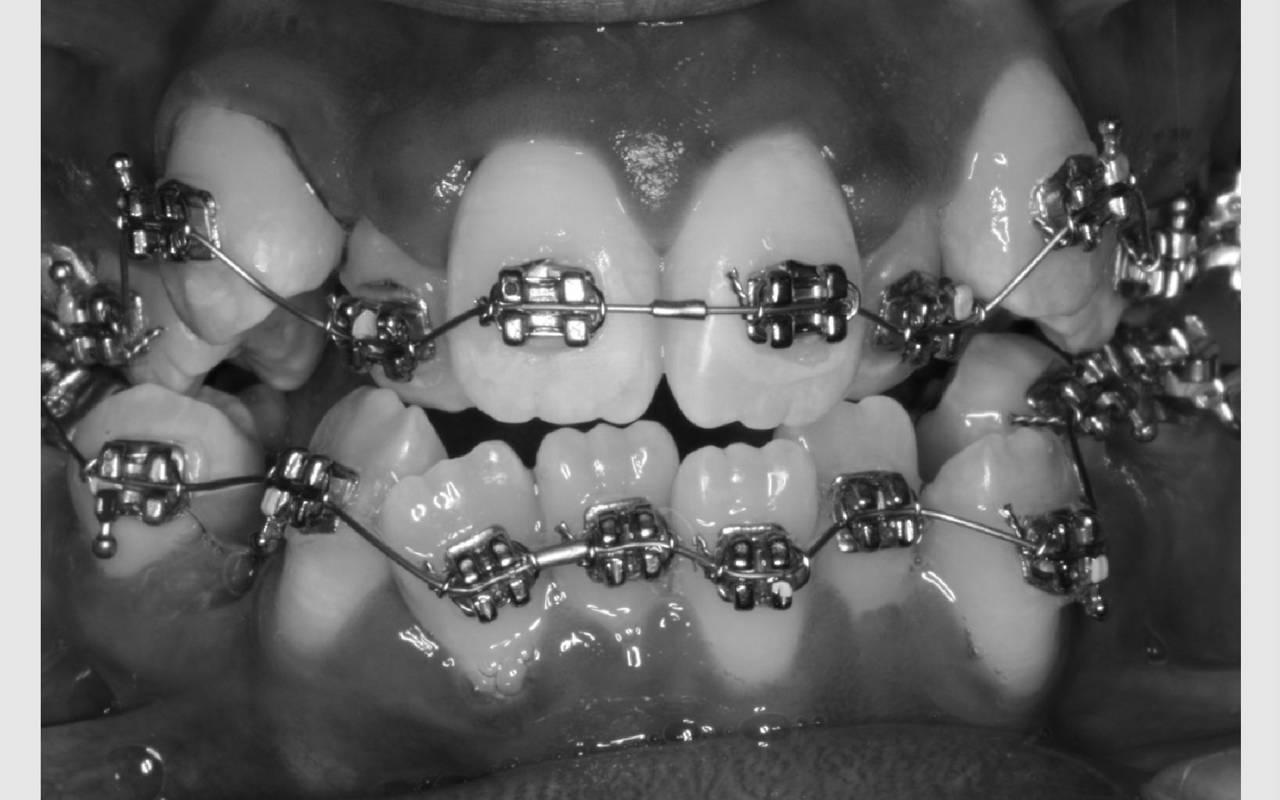

Faste bøjler - "togskinner"

Ofte er der brug for fastsiddende bøjler på tænderne. Mange kalder dem "togskinner", hvilket er et passende navn, da tænderne nærmest bliver flyttet i et spor på den lås, der limes på tanden.

Det gør ikke ondt, men det tager lang tid at lime låsene på tænderne, da de skal sidde helt præcist. Så du skal være indstillet på at ligge i tandlægestolen i en times tid. Synes du, det lyder som lang tid, kan du tage høretelefoner på og høre musik samtidig.

Sådan bliver bøjlen sat på

Før låsene limes på, bliver tænderne pudset helt glatte. Herefter bliver overfladen gjort klar til limen med en blå gele, der skal ligge på tænderne i 30 sekunder. Der skylles med vand og blæses helt tørt, hvorefter låsene kan limes fat på tænderne. Limen er en form for plast, der svarer nogenlunde til den plast, man bruger til tandfyldninger.

For at plasten kan hærde, lyses der på tanden med ultraviolet lys i 20 sekunder. For at beskytte vores øjne mod det ultraviolette lys, bliver der holdt en orange skærm for øjnene. Når alle låse er limet på, forbindes de med en bue af metal. Det er den, der flytter på tænderne.

Når bøjlen har siddet på i nogle timer, vil tænderne begynde at blive ømme. De fleste oplever let smerte i en lille uge, hvorefter ømheden forsvinder. Når du får strammet bøjlen, kan tænderne igen blive lidt ømme i en dag eller to. For langt de fleste er tandretning dog ikke forbundet med megen smerte.

Efter bøjlen er blevet sat på, får du vist, hvordan du bedst holder tænder og bøjle ren. Du får også gode råd om kost.